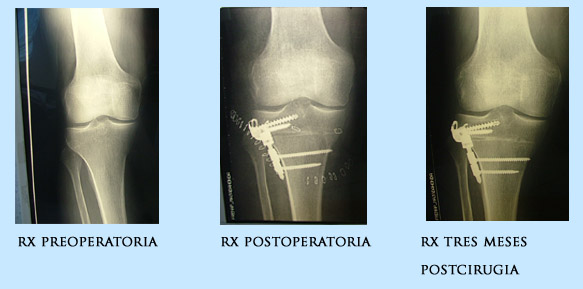

ose-031º caso: J.SJ. C. Varón 31 años rodilla derecha.

Antecedentes Q: 1997 Meniscectomia interna.

1999 Plastia LCA

Cirugía 12.04.04: Injerto autólogo ST + RI (tetrafascicular): Rigidfix.

Osteotomía Valguizante sustracción con placa VCO.

ose-042º caso: F.A.V. Varón 43 años rodilla derecha.

Antecedentes Q: 2001: Menicectomia interna

Cirugía 03.02.03: Injerto autólogo ST + RI (tetrafascicular): Rigidfix.